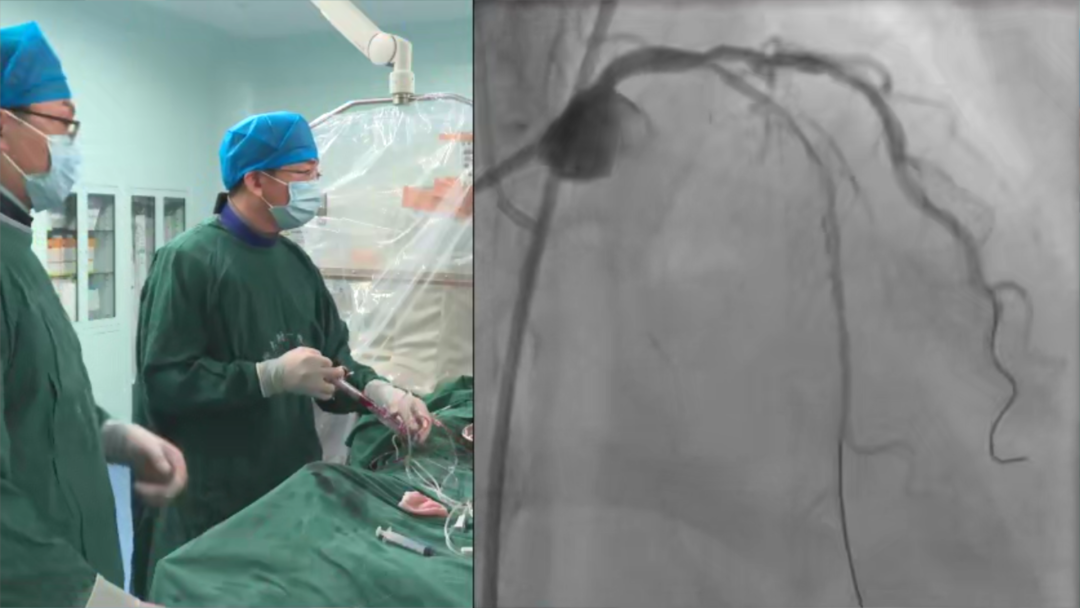

实践方能出真知,结合影像学技术在复杂冠脉介入手术中的应用,中国科学技术大学附属第一医院 (安徽省立医院) 马礼坤教授带来了一例CTO病例分享,直观地展示了飞利浦心血管整体解决方案在CTO介入手术中的卓越临床价值。

马礼坤教授手术患者为一名老年女性,因“胸闷、心悸、头晕一月余”入院,曾外院造影前降支开口80%狭窄,中段闭塞;回旋支开口至中段狭窄90%,右冠中段狭窄80%,后降支向前降支提供侧枝。既往有糖尿病5年,长期二甲双胍联合胰岛素控制血糖。心脏超声提示:LA40mm,EF66%。

术中,马礼坤教授首先在严重狭窄的回旋支近端进行扩张,减少左冠反复操作过程中缺血的可能性。仔细阅片后选择了FINECROSS 15微导管到闭塞段,PILOT150导丝进入病变通过闭塞段到达远端腔,继续交换微导管和导丝,球囊扩张闭塞段。接下来,关于植入支架和术式的选择,马礼坤教授首先应用IVUS观察病变特征,发现前降支闭塞段相对于左主干及回旋支明显更细,斑块及钙化更严重,经过讨论后决定采用DK-Crush术式,分别在前降支和回旋支植入2.5*36mm支架,回旋支Crush前降支,考虑到近端还有一些斑块,植入4.0*20mm的支架,近端进行POT,球囊后扩,完成手术。

术后,马礼坤教授分享了本例CTO PCI手术成功的关键,他认为此次手术成功的主要原因有三点:

1仔细阅片,本例病例前降支CTO,左主干远端分叉病变,仔细阅片后发现前降支闭塞段不是太长,并且有锥形头,给导丝和术式的选择提供了依据。

2借助腔内影像学工具评估,本病例采用IVUS评估,前降支闭塞处直径小,而左主干和回旋支相对更大,因此选择DK-Crush术式。使用IVUS可以对支架的选择和贴壁程度进行很好的判断。

3强大的血管造影显像系统,马礼坤教授强调,此次使用的是最新一代的Azurion图像引导治疗平台,具有成像质量高,透视辐射小,操作便捷等特点,在手术中如虎添翼,为PCI手术的成功打下基础。